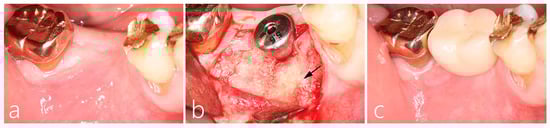

2.2. Uncovering Procedure